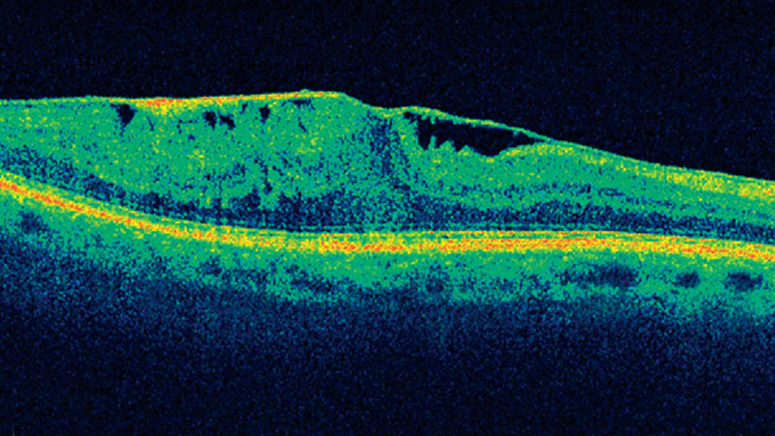

Οι ασθενείς μπορεί να μην γνωρίζουν ότι πάσχουν από την συγκεκριμένη πάθηση γιατί κάποιες φορές δεν προκαλεί συμπτώματα, έως ότου παρατηρηθεί σε μια τυπική οφθαλμολογική εξέταση. Με την οπτική τομογραφία συνοχής (OCT) μπορεί ο οφθαλμίατρος να καταλάβει πόσο σοβαρή είναι η κατάσταση της πάθησης. Με την συγκεκριμένη μέθοδο λαμβάνονται φωτογραφίες υψηλής ανάλυσης των ματιών σας. Μια άλλη μέθοδος είναι η φλουοροαγγειογραφία.